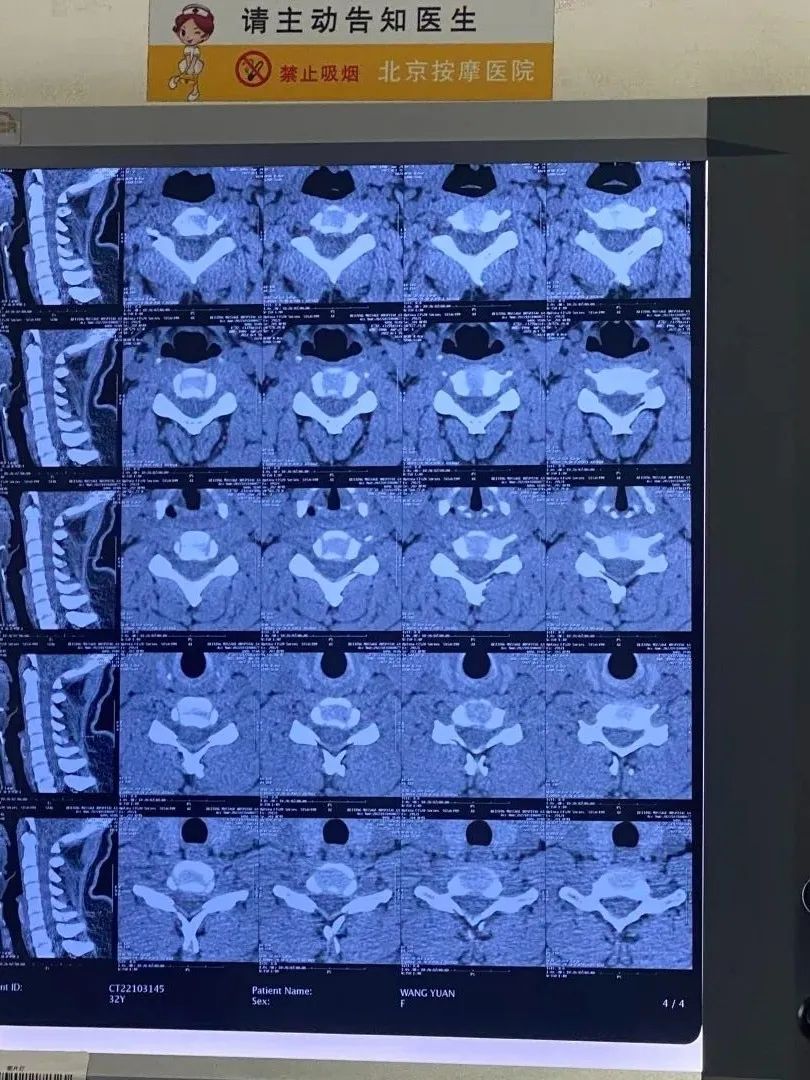

一个变直的颈椎CT